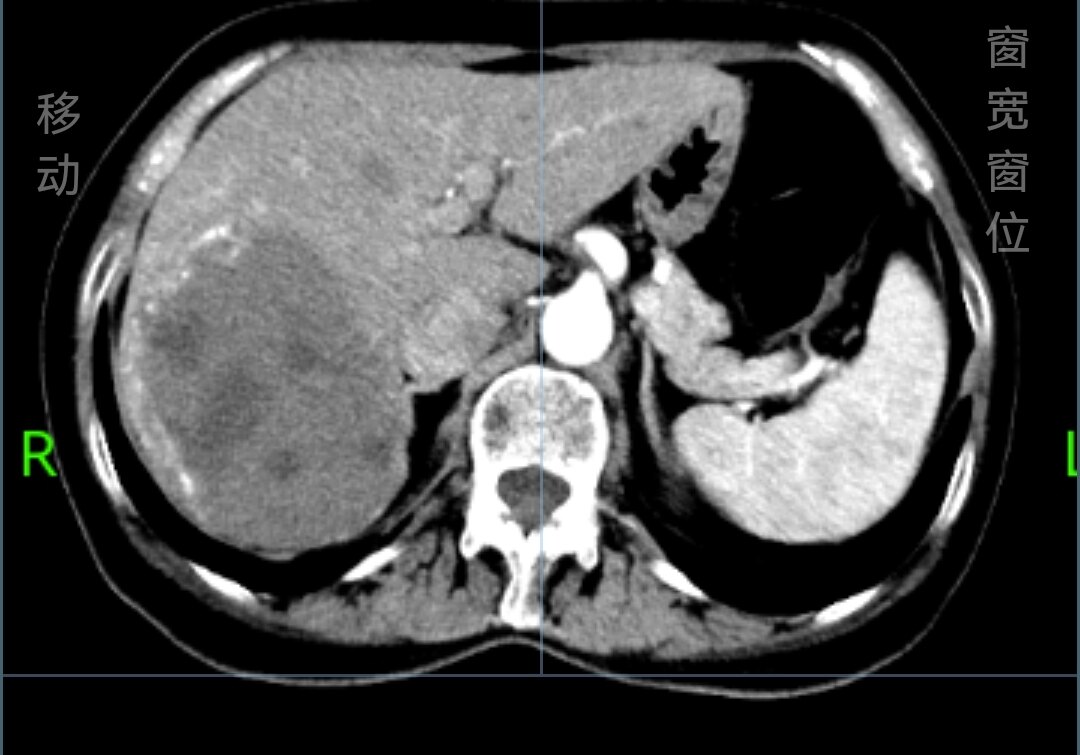

术前CT见右肝后叶9.5cm血管瘤

肝脏血管瘤超过5cm,如果近期有持续明显增大,无手术禁忌,可以选择

腹腔镜血管瘤切除术。